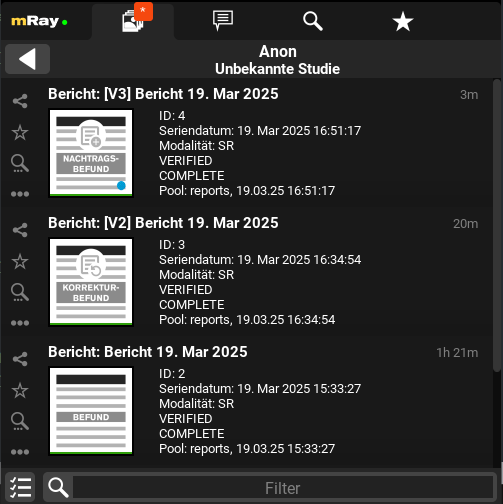

Supplementary and corrective findings are now clearly separated from each other

12.6. Corrective and Supplementary Report

Approved reports cannot be modified; however, it is possible to create a corrective or supplementary report. These reports are versioned, ensuring that the original approved report remains unchanged.

To create a corrective or supplementary report, click the Edit button located at the bottom right corner of an approved report. You will then be prompted to select the type of report you wish to create.

12.6.1. Corrective Report

A corrective report allows a complete modification of the text of an already approved report.

12.6.2. Supplementary Report

A supplementary report permits the addition of new information to the report, but only once. The existing text remains unmodifiable.

12.6.3. Report History

Both corrective and supplementary reports retain the history of their previous versions. These versions can be accessed through the series view of a study. To open the series view, refer to Series selection.